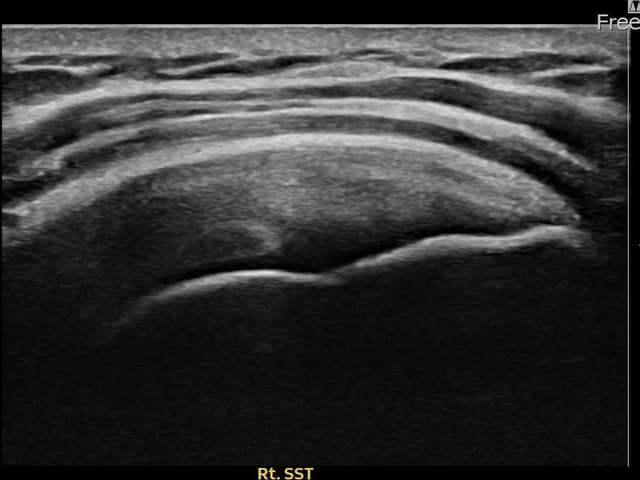

[経過期間: 24.03.21~24.05.29]

[縫縮術] 超音波検査にて右 견갑하근건 部分断裂(8mm × 3mm (腱厚の約32%欠損))を確認。縫縮術施行後、腱の連続性が回復し、日常生活に復帰されました。